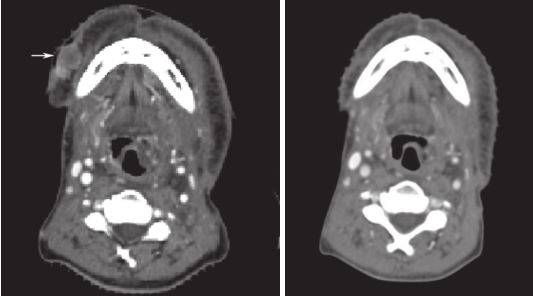

疗效评估:一线方案治疗后,患者出现严重副作用,终止肿瘤治疗,治疗后3个月评估局部肿瘤控制达CR(图5),但发现腋窝淋巴结增大,故总体疗效评估为肿瘤进展(PD)。鉴于患者一线治疗失败,更换二线单药化疗方案,联合西妥昔单抗靶向治疗。治疗结束后一段时间失访,直到2021年(复发转移后PFS超过3.5年)随访,患者目前一般状态可,生活质量好。

图5 右下颌骨前方结节治疗后达完全缓解